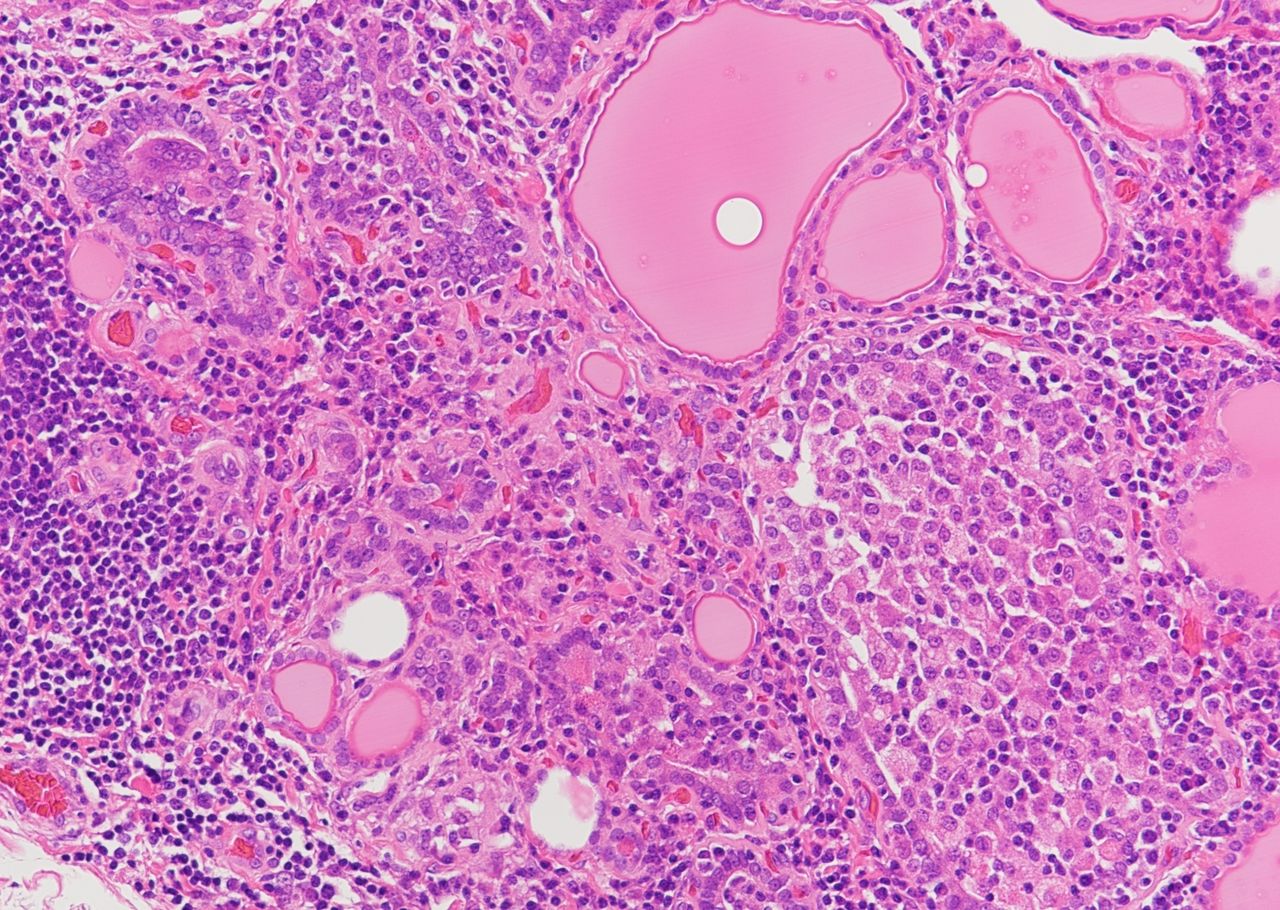

A 45-year-old female patient presented with features of hypothyroidism. Based on the provided histological features, what is your diagnosis?

Explanation: ***Hashimoto thyroiditis*** - Classic histological features include **lymphocytic infiltration** with **germinal center formation** and **Hürthle cell metaplasia**, consistent with hypothyroidism in a middle-aged female. - Shows **follicular atrophy** and **fibrosis**, leading to gradual thyroid dysfunction and is the most common cause of hypothyroidism in iodine-sufficient areas. *Granulomatous thyroiditis* - Characterized by **epithelioid granulomas** and **giant cells** histologically, not lymphocytic infiltration with germinal centers. - Typically presents with **painful thyroid enlargement** and **transient hyperthyroidism** followed by hypothyroidism, rather than primary hypothyroidism. *Papillary carcinoma of the thyroid* - Shows **papillary architecture** with **psammoma bodies** and **nuclear features** like overlapping, grooves, and pseudoinclusions. - Usually presents as a **thyroid nodule** rather than diffuse hypothyroidism, and patients are typically **euthyroid**. *Riedel's thyroiditis* - Characterized by **dense fibrous tissue** replacing thyroid parenchyma with **woody hardness** on palpation. - Shows **storiform fibrosis** without significant lymphocytic infiltration or germinal centers, and often involves surrounding structures.